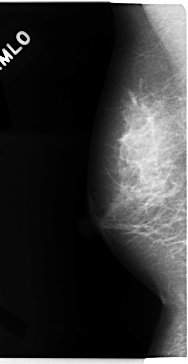

C_0113_1.RIGHT_MLO

RIGHT_MLO LINES 4728 PIXELS_PER_LINE 2432 BITS_PER_PIXEL 12 RESOLUTION 50 NON_OVERLAY